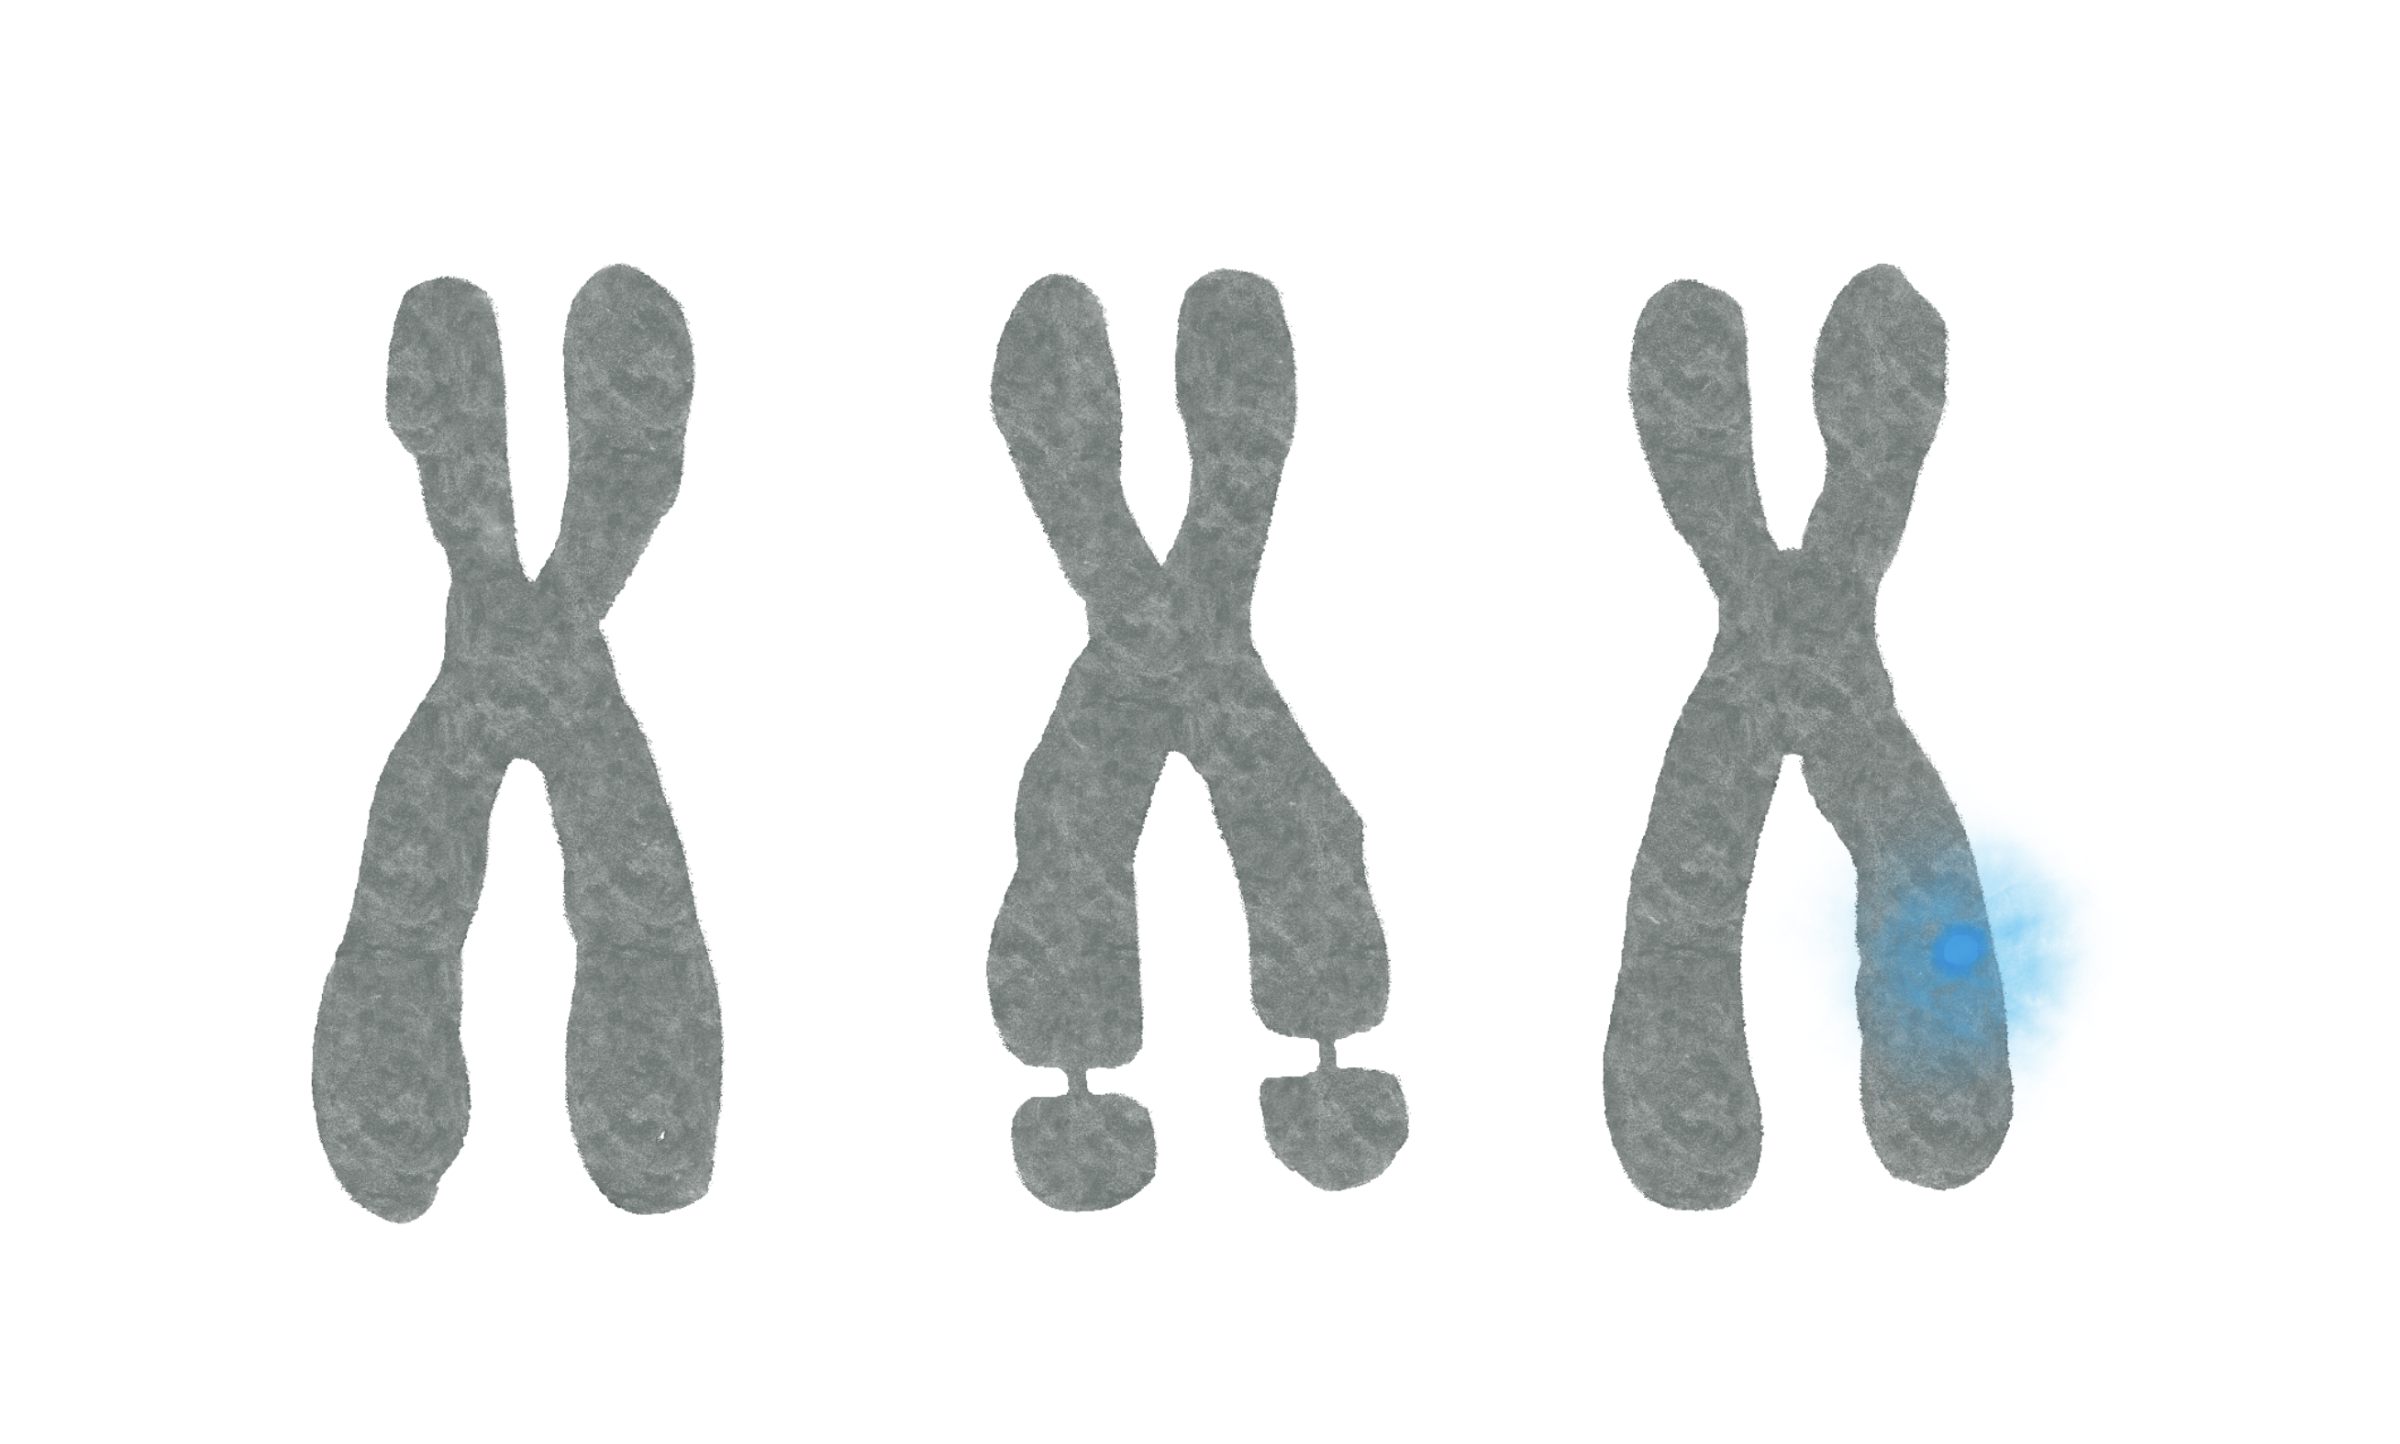

Chromosomes

Carrier of genetic trait

Cystic fibrosis and Fragile X syndrome